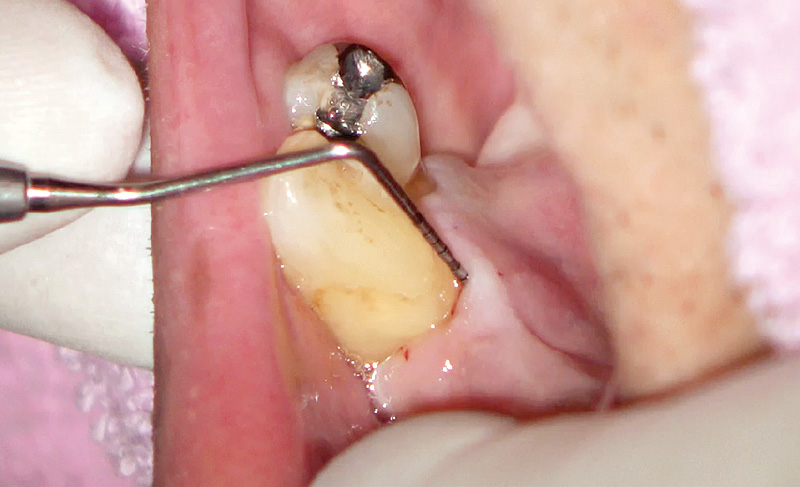

基本的に痛くなってからしか来ない患者の典型的症例(図3)。残存している下顎右側犬歯と第一小臼歯臼歯間のサイナストラクト発症により来院。側枝からの感染による歯髄壊死も考えられたため、ガッタパーチャを挿入後に、デンタル撮影にて部位特定。歯周病急性症状改善後、歯周ポケット測定を行うと舌側中央に8mmのポケットを確認した(図4)。

プリセットモード「歯石除去」にてS600Tのチップを用いてディープスケーリング5)を行った(図5)。縁下内部をEr:YAGレーザーで照射、スケーリングしていくと、内部から縁下歯石がポケット外へ飛び出してくる。S600Tを用いることにより、ポケット内縁上皮も掻爬され健全な根面を得ることができた(図6)。

図4 43舌側プロービング時口腔内写真。舌側中央に8mmのポケットが確認できる。 -